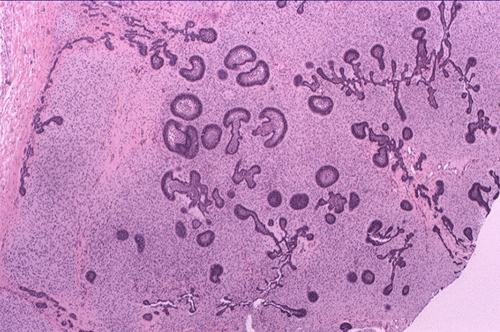

The panoramic view demonstrated a mulilocular lesion in the left ramus of the mandible. The lesion is well defined and without much sclerotic changes at the rim. The first molar is unerupted and is associated with the lesion (arrow in Panel A). On histologic section, the lesion is composed of a solid mass with numerous thin, anastomosing trabecula or cords of epithelial cells. At the and of these branching anastomosis, there the epithelial component tend to expand a little and form a small island. No larger islands are noted (Panel B and C). No calcification or eosinophilic depositions are noted in the epithelial islands. There is no microcyst formation in the epithelial component and the overall pleomophism is minimal . The embedding stroma is composed of a moderately cellular, stellate shaped, rather monotonous proliferation of cells without high grade nuclear features nor mitosis.

Grossly, these tumors occur as solid, soft tissue mass with or without a capsule. Histologically, there are anastomosing cords and of low-histologic grade epithelium that resemble odotogenic epithelium embedded within a background of cellular mesenchyma that resembles primitive dental papilla. The mesenchymal component is composed of plump stellate cells and ovoid cells in a loose matrix with little collagen deposition albeit diffuse hyalinization can be seen. The anastomosing cords are often two-cell thick cuboidal or columnar epithelium. Less commonly, the epithelial component appears as small, discret islands characterized by a peripheral rim of columnar cells surround a central core of stellate cells and such arrangement mimics the follicular stage of developing enamel organ. Microcyst formation is rarely seen in these islands and is a feature that distinguishes AF from follicular variant of ameloblastoma. Hyalinization around the epithleial cords and islands may be present.